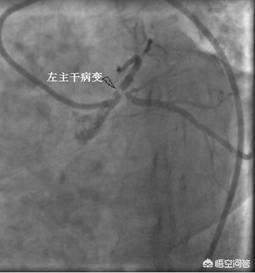

①明確な診断冠動脈性心疾患の診断は、現在の医療レベルでは、次のような方法で難しいことではない。冠動脈造影冠動脈疾患の確定診断ができる。冠動脈に直接カテーテルを通し、造影剤を出して冠動脈を画像化することで、閉塞の場所や程度が明確になり、その後の治療の根拠となります。これが冠動脈疾患の最も一般的な治療法である理由です。冠動脈疾患診断の "ゴールドスタンダード"。。

狭心症の症状、トロポニンの上昇、心電図の変化などは冠動脈疾患のスクリーニングに有用であるが、冠動脈疾患の診断のゴールドスタンダードは冠動脈造影検査である。冠動脈造影検査は侵襲的な手技であるが、冠動脈疾患の診断と重症度の把握にかけがえのない役割を担っている。冠動脈造影検査は造影剤を注入することによって、冠動脈の狭窄の程度をはっきりと観察することができ、冠動脈の狭窄が50%に達すると冠動脈性心臓病と診断することができます。 冠動脈造影検査は同時に冠動脈の病変部分と量を把握することができ、病態を評価するための非常に貴重な手がかりを提供することができます。冠動脈疾患は治るのか?現在の医療技術では、冠動脈疾患を治すことはできません。しかし、アスピリンやクロピドグレルなどの抗血小板凝集薬、スタチンなどのプラーク安定化薬、ベタブロッカーやプリリジーなどの予後改善薬などの合理的な治療により、心筋梗塞に移行するリスクを減らすことは可能です。冠状動脈性心臓病

まとめると、狭心症、トロポニンの上昇、心筋虚血を示唆する心電図は冠動脈疾患のスクリーニングに有用である。 しかし、冠動脈疾患の診断のゴールドスタンダードは冠動脈造影であり、50%までの冠動脈狭窄が冠動脈疾患の診断となり、同時に冠動脈病変の位置と数を把握することができる。冠動脈疾患は治すことはできないが、妥当な治療によって冠動脈疾患の進行を遅らせ、心筋梗塞のリスクを減らすことができる。